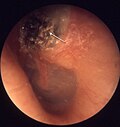

Image:Cholesteatom_kuppelraum_1a.jpg | Cholesteatoma. (WC) | Image:Cholesteatom_kuppelraum_1a.jpg | Cholesteatoma. (WC) | ||

| Signs | whitish mass in the middle ear |

- Whitish mass in the middle ear.[8]

Image